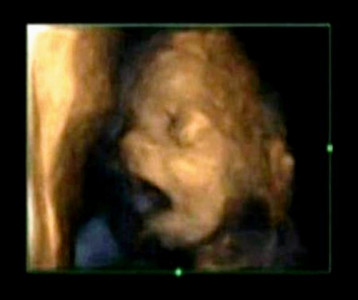

Japan firm offers 3D model of foetus

Expectant parents who can't wait to show friends what their baby will look like can now buy a 3D model of foetus.

4D scans show fetuses yawn in the womb

Researchers used 4D video footage to examine all the times when foetuses opened their mouths.